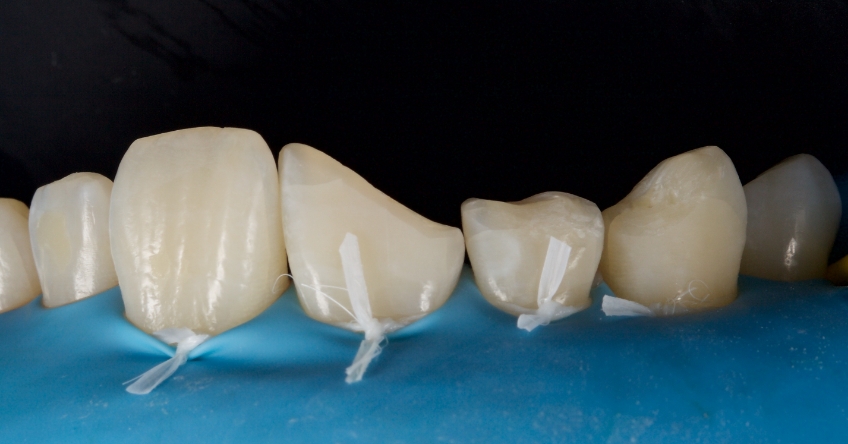

Any biofilm and aprismatic enamel were removed from the tooth, and the fragment was fragmented with light hydro abrasion with 29-micron alumina at 2-3 bar pressure. The tooth and the fragment were etched with 37% phosphoric acid (Ultradent), and a fourth-generation dentin bonding agent (Kerr, OptiBond FL) was applied (the adhesive component was not light-cured).

The fragment was luted to the tooth with heated chromatic enamel shade composite (GC G-aenial A2 shade). The heater used was a Calset Warmer from Addent. The excess composite was cleaned with an interproximal carver from American Eagle and smoothed with a number three brush and modeling resin (Brush & Sculpt from Cosmedent).

The composite was heated because it gained lower viscosity to improve adaptation. Plus, heating increases the conversion of monomer to polymer, which improves the physical characteristics of the resin, such as flexural strength and wear resistance, according to research by Da Costa, Hilton, and Swift in 2011.

The resin was polymerized, and the oxygen-inhibited layer was removed by polymerization under glycerine.

The enamel fracture on 2.1 was untouched and will be managed in conjunction with esthetic management of the white hypo calcification at a later time.